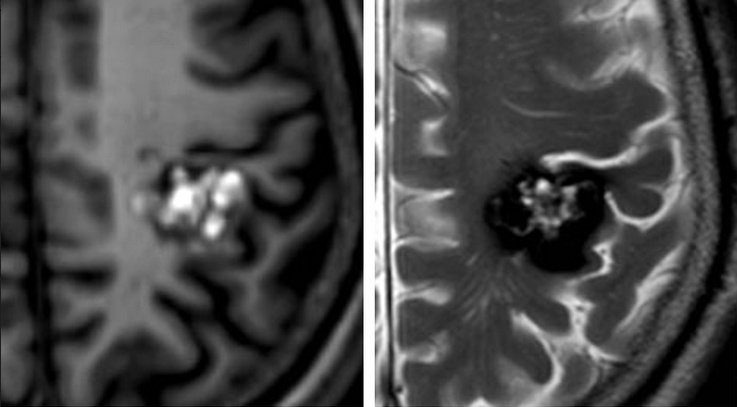

A cavernous malformation (also called a cavernoma or cavernous angioma) is a cluster of abnormally formed, thin-walled blood vessels in the brain or spinal cord. Unlike AVMs, cavernous malformations are low-flow lesions—they do not have the high-pressure arterial blood flow that makes AVMs dangerous. However, they can bleed (usually small hemorrhages), causing headaches, seizures, and neurological deficits depending on their location.

Notably, cavernous malformations are typically invisible on catheter angiography, which distinguishes them from AVMs and dural fistulas.